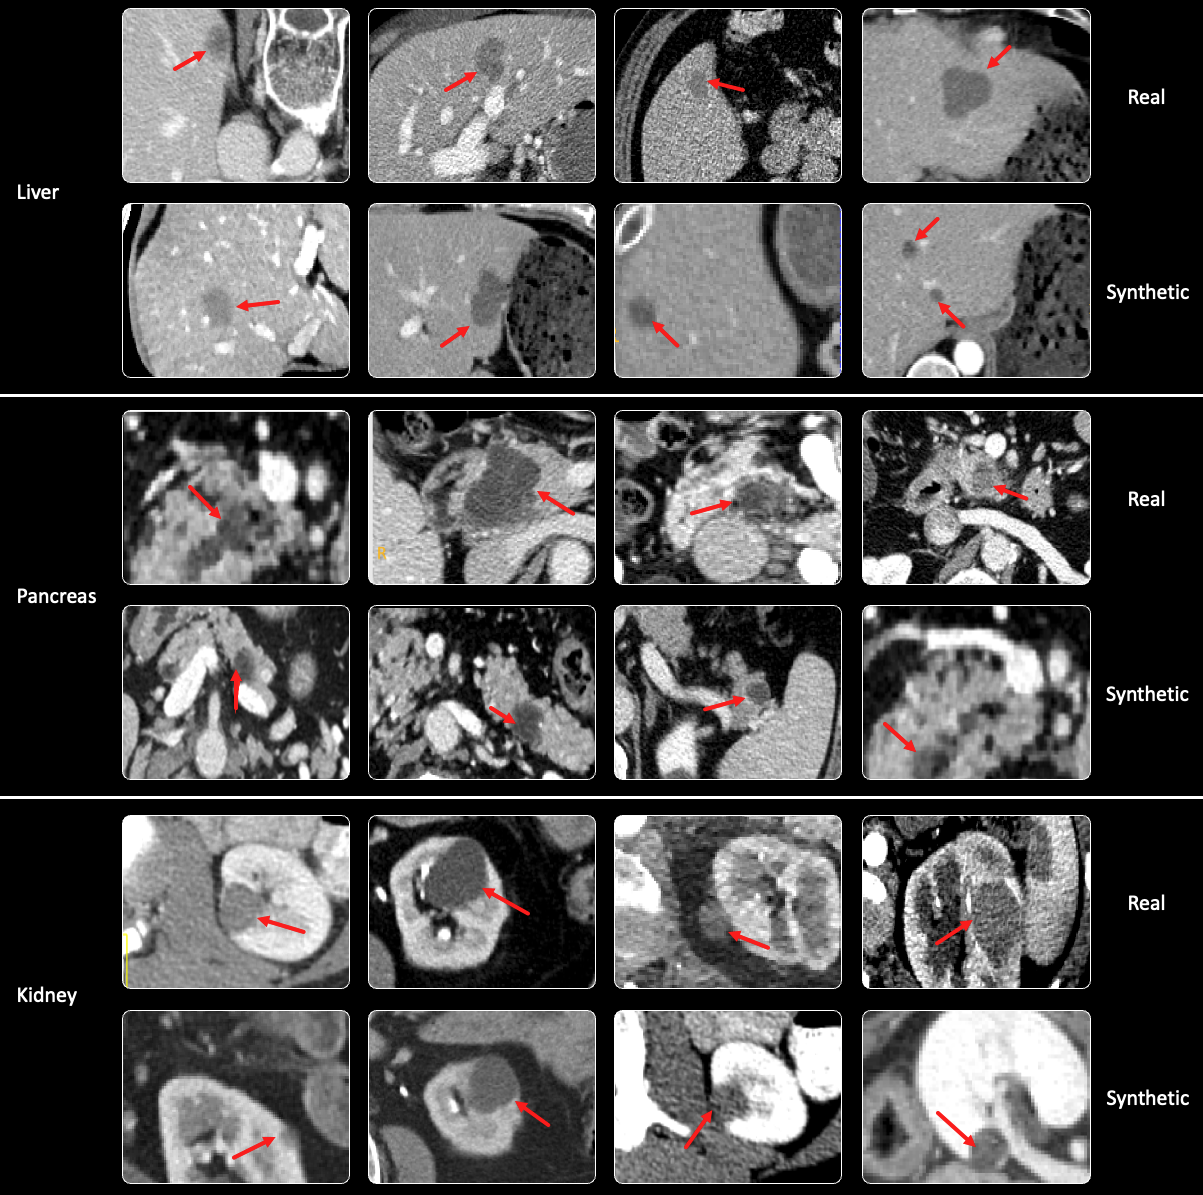

Clinical Validation: We performed a Visual Turing Test [geman2015visual] on 150 CT images, including 25 images with real tumors and 25 images with synthetic tumors in each organ test set. The results in Table 1 show performance metrics for different radiologists. Radiologist R1 (3 years experience) only achieves specificity below 30%percent3030\%. R2 (7 years) exhibits specificity around 50%percent5050\%, confusing half of the synthetic tumors. Even R3 (10 years) misidentifies 47.1%percent47.147.1\% of synthetic tumors as real. This demonstrates the realistic tumor simulation achieved by Pixel2Cancer.

Table 1: Visual Turing Test is conducted by three experts, each evaluating 150 CT images, with 50 images allocated for each organ. They were tasked with categorizing each CT image as either real, or synthetic. A lower specificity score indicates a higher number of synthetic tumors being identified as real.

Refer to caption

Figure 4: Examples of early tumor detection. Qualitative visualizations of segmentation models for liver, pancreas, and kidney tumor detection.

Figure 5: Examples of Visual Turning Test. Tubular results are presented in Table 1. Our Pixel2Cancer can be used to augment available healthy CT volumes [li2024well, qu2023annotating].